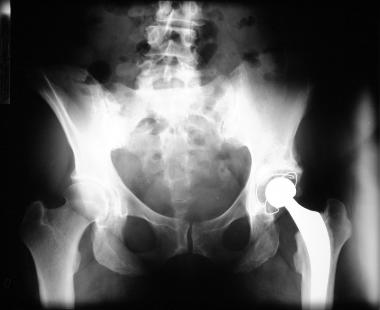

Le prix Galien 2010, dans la catégorie « Médicaments destinés à la thérapeutique ambulatoire », a été décerné au rivaroxaban (Xarelto, Bayer Schering Pharma), un anticoagulant actif par voie orale et n’imposant pas de contrôle biologique. De nombreuses études, dont RECORD 1 et 3, ont montré son intérêt dans la prévention des événements thromboemboliques veineux après prothèse de hanche ou de genou. Il permet de remplacer l’injection sous-cutanée d’anticoagulant héparinique par l’administration orale d’un comprimé.

Prothèse totale de hanche

Une AMM européenne centralisée a été octroyée le 30 septembre 2008 dans l’indication « prévention des événements thromboemboliques veineux chez les patients adultes bénéficiant d’une intervention chirurgicale programmée de la hanche ou du genou (prothèse totale de hanche ou du genou) ». En France, l’autorisation de mise sur le marché a été entérinée en mai 2009.

De nombreuses études ont prouvé l’intérêt du rivaroxaban dans la prévention des événements thromboemboliques veineux (ETEV). Il s’agit notamment des études RECORD 1 et 3 chez 6?800 patients (1, 2). L’efficacité du rivaroxaban y est apparue supérieure à celle de l’énoxaparine, administrée à la dose de 40 mg par voie sous-cutanée après prothèse totale de hanche ou de genou. Aucun excès de risque hémorragique n’est apparu.